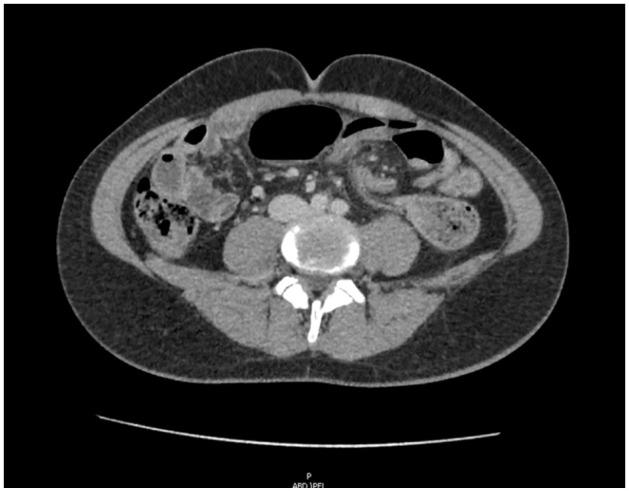

15岁男性乙状结肠扭转的内镜下复位术

Endoscopic Reduction of Sigmoid Volvulus in a 15-Year-Old Male.

Sigmoid volvulus is a well-recognized phenomenon in the elderly but rare in children. The proposed mechanism involves rotation of a redundant sigmoid loop around a narrow, elongated mesentery with subsequent vascular occlusion. The condition can be intermittent or may resolve spontaneously, complicating diagnosis. Early diagnosis is imperative to prevent ischemic complications including necrosis, perforation, and sepsis. Abdominal pain, abdominal distention, and vomiting are the most common presenting symptoms, however abdominal tenderness is uncommon. Colonic dilation is the most frequent finding on abdominal radiograph. Contrast enema reveals a "bird's beak" configuration of the twisted colon and moreover, is successful in reducing the majority of pediatric cases. If there is no evidence of bowel ischemia or perforation, endoscopic reduction has been proposed as first-line treatment for sigmoid volvulus, especially in children. We report the case of 15-year-old male in which endoscopic reduction of sigmoid volvulus was successful without complication.

摘要

乙状结肠扭转在老年人中是一种广为人知的现象,但在儿童中罕见。其推测机制包括一个冗长的乙状结肠袢围绕狭窄、细长的肠系膜旋转,随后发生血管闭塞。这种情况可以是间歇性的,也可能自行缓解,这使得诊断变得复杂。早期诊断对于预防包括坏死、穿孔和败血症在内的缺血性并发症至关重要。腹痛、腹胀和呕吐是最常见的症状表现,然而腹部压痛并不常见。结肠扩张是腹部X线片上最常见的表现。钡剂灌肠显示扭转结肠呈“鸟嘴”状,而且,大多数儿科病例通过钡剂灌肠复位成功。如果没有肠缺血或穿孔的证据,内镜复位已被提议作为乙状结肠扭转的一线治疗方法,尤其是在儿童中。我们报告了一例15岁男性患者,其乙状结肠扭转经内镜复位成功且无并发症。